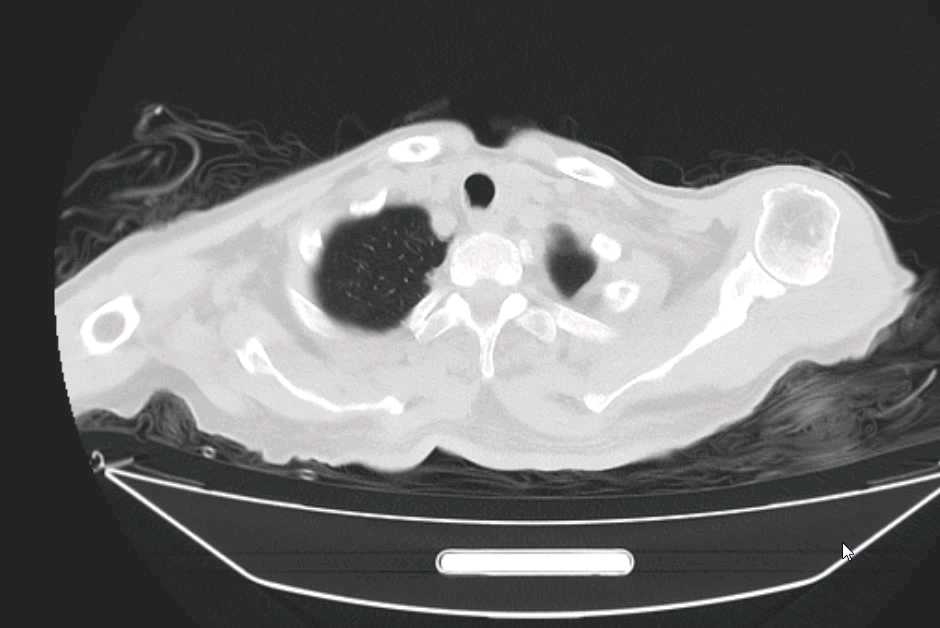

4、辅助检查:(2024-07-16)血常规示:白细胞计数:14.09x10^9/L↑;中性粒细胞绝对值:12.96x10^9/L↑;淋巴细胞绝对值:0.85x10^9/L↓;嗜酸性粒细胞绝对值:0.01x10^9/L↓;中性粒细胞百分比:92.00%↑;淋巴细胞百分比:6.00%↓;单核细胞百分比:1.90%↓;嗜酸性粒细胞百分比:0.10%↓;凝血功能示:纤维蛋白原降解:15.49ug/ml↑;D一二聚体:1.41ug/ml↑;心肌两项示:肌红蛋白:410.5ng/ml↑;N末端B型钠尿肽前体:3422pg/ml↑;呼吸道八联检查:甲型流感病毒:弱阳性+;电解质示:钠:130.7mmol/L↓;磷:0.55mmol/L↓;肝功能示:总胆红素:34.8umol/L↑;直接胆红素:14.7umol/L↑;间接胆红素:20.1umol/L↑;胆碱酯酶:4441U/L↓;肾功能示:尿素氮:8.54mmol/L↑;肌酐:171.9umol/L↑;血清胱抑素C:1.777mg/L↑;心肌酶四项示:肌酸激酶:352.3U/L↑;乳酸脱氢酶测定(速率法等):264.6U/L↑;α-羟丁酸脱氢酶:198U/L↑;心电图示:1、窦性心动过速;2、肢导联低电压;3、V6导联T波轻度改变。颅脑及双肺CT示:1、颅脑CT平扫未见异常,必要时请复查。2、左肺上叶下舌段及右肺中叶外侧段感染性病灶。3、心脏外形不大,主动脉壁及左侧冠状动脉走行区多发钙化斑。随机血糖:9.1mmol/L。

患者持续发热,激素,退热针,左氧氟沙星,派拉西林都无法退热,给予完善腹部ct及b超

目前来看bnp持续升高及肾脏,心肌酶,降钙素原持续升高,原因何在?请各位从影像上分析: